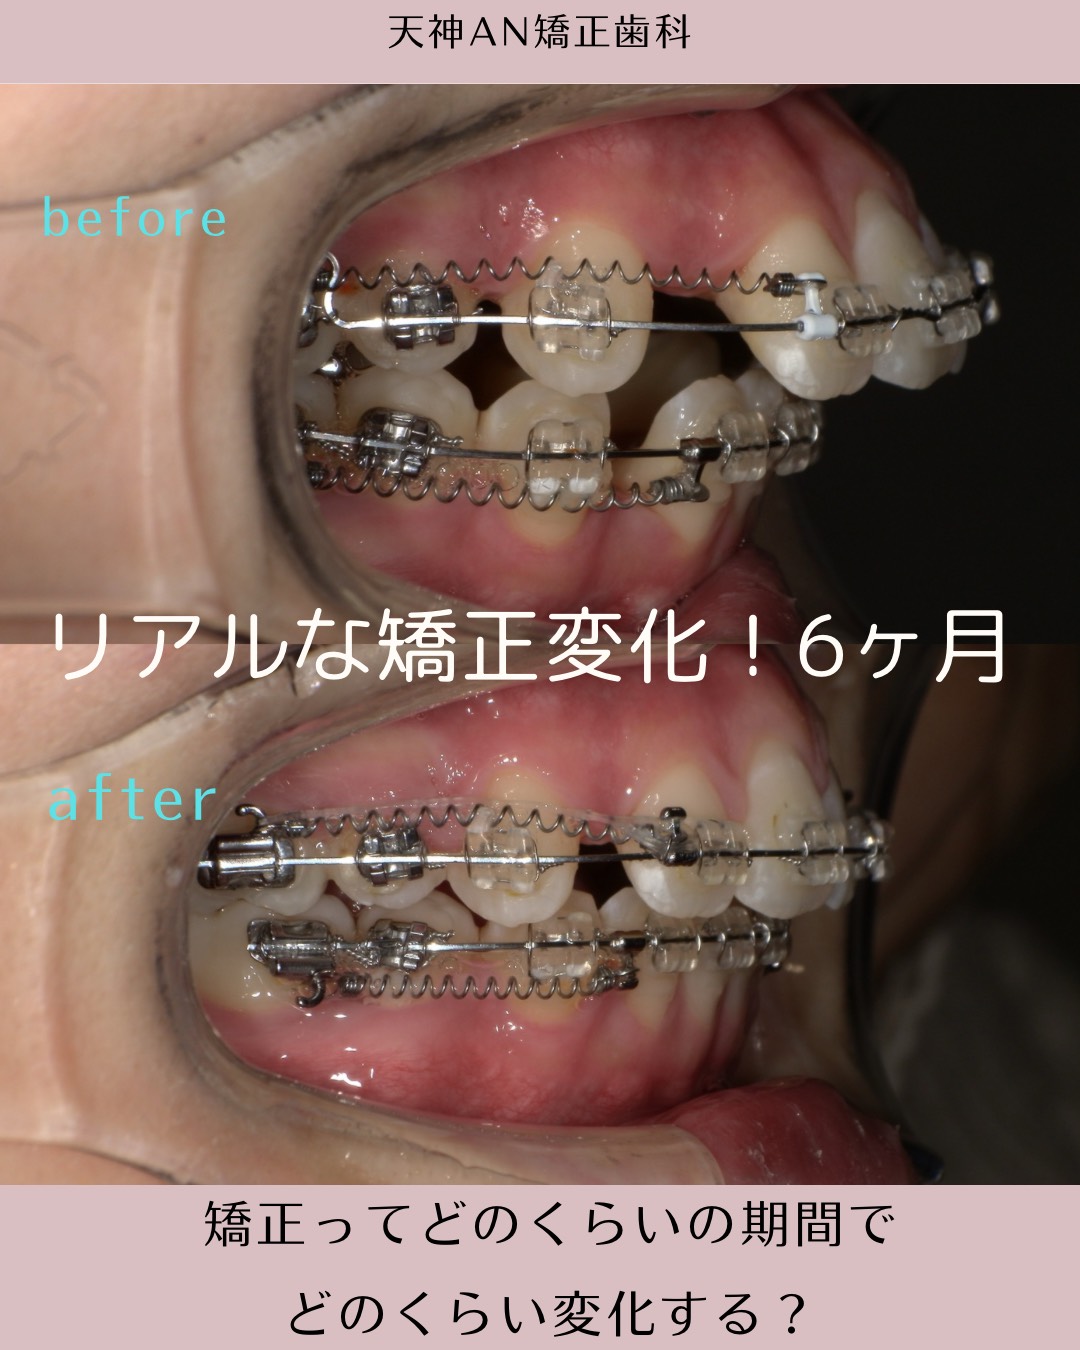

今回の写真は、

抜歯矯正約6ヶ月時点のリアルな変化。

まだ治療途中にも関わらず、

歯の並び・噛み合わせ・骨の前突傾向にはっきりとした改善が見られます。

今回の症例で起きている変化ポイント

写真を見ていただくと、

前歯の傾きが内側に入る

- 骨ごと歯が引っ込んでいる→口元も変化しています

- 噛み合わせのズレが改善方向へ→1本対1本で嚙んでいたのが1本対2本のかみ合わせへ

「6ヶ月でここまで変わるんですか?」とよく聞かれます